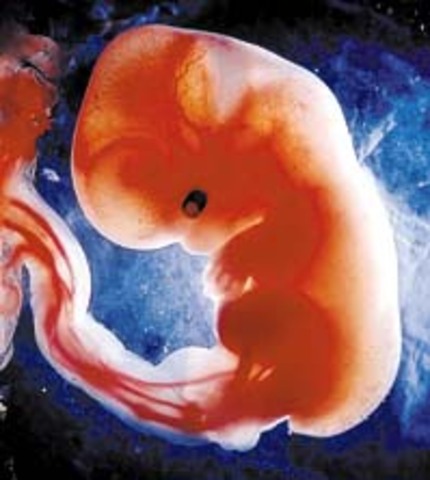

• End of First Month

End of First Month

• The brain, spinal cord, lungs, and heart begin to form

• Heart is forming

Heart is forming

During the first few weeks after conception, the fetal heart occupies most of the fetus' mid-section. The heartsize to bodysize ratio is nine times greater in the fetus than in the infant. During those first few weeks, the fetal heart lies high in the chest. Soon, it moves down to occupy its position in the chest cavity.

• Face development

Face development

the face is starting to take shape after 3 weeks from fertilization

• Digestive tract begins to form

Digestive tract begins to form

In the fourth week of embryonic development, the digestive system begins to develop with the formation of what is called the "primitive gut."

• Backbone begins to develop

Bones appear during week 5 as mesenchymal condensations in the limb buds

• arms and legs develop

arms and legs develop

The embryo's arms and legs begin to grow from buds at each side. At first the hands and feet are shaped like paddles.